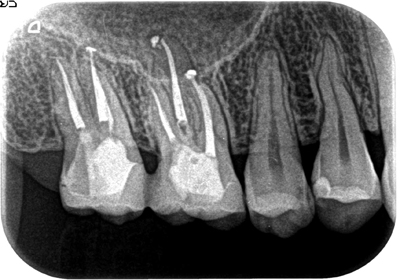

症例1【30代女性】右上7番根尖相当部に大きな病巣がみられ、副鼻腔の粘膜にも波及し、肥厚している。15ヶ月後、病巣はほぼ消失し、骨が再生、副鼻腔粘膜の肥厚も消失。

治療後(15ヶ月後)

治療後

2Dのレントゲンではわずかな病巣としか見えませんが、3DのCTでは内部にかなり大きな病変が在るのが良くわかります。